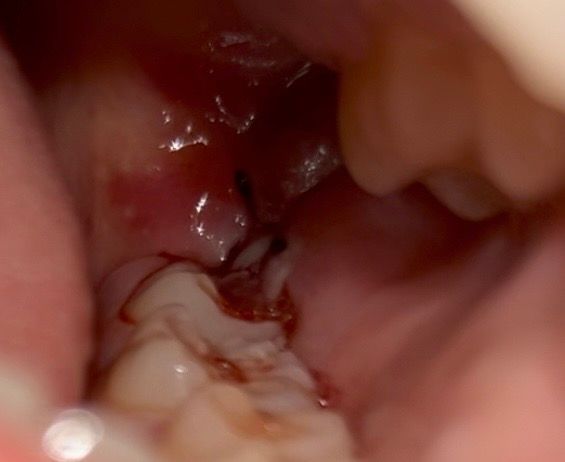

매복사랑니 발치 4일차 출혈 정상인가요

심한 출혈은 첫날 멈췄는데

이정도 출혈이 지금까지 한 번도 안멈추고 계속 납니다 욱신거리기도 하고요 언제 멈출까요?

• 1번 째 사진

매복사랑니 발치 4일차라면 사진에서 정도의 출혈량은 나올 수도 있습니다. 괜찮을겁니다.

발치하신지 4일이 지낫는데 피가 저정도면 지혈이 잘안되시거 같은데 치과에 가셔서 소독을 한번 다시 받아보세요.

4일후 에도 출혈이 된다면 발치를 한부위가 자극이 되어 상처가 났을수 있습니다. 거즈를 물고 있는것이 좋으며 해당부위가 자극이 되지 않도록 하는것이 좋습니다.